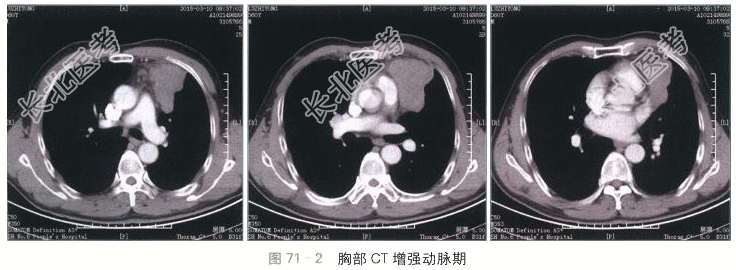

- [材料题] 患者,男性,60岁,胸前区隐痛不适半年。体格检查:呼吸音清,胸前区无明显扣痛。实验室检查:血常规、肝肾功能及肿瘤标志物均正常。胸部CT扫描(见图71-1~图71-3):提示左前纵隔软组织密度肿块,形态不规则,边缘可见分叶和波浪样改变,密度较均匀,CT值约45Hu,增强后动脉早期轻度强化,CT值约54Hu,延迟期可见显著持续渐进性强化,CT值约82Hu。肿块局部层面与肺动脉及左心耳分界不清,脂肪间隙消失。

读片分析:本例患者的病灶定位于前纵隔,前纵隔好发的肿瘤及肿瘤样病变包括胸骨后甲状腺肿、胸腺囊肿、胸腺瘤、胸腺癌、淋巴瘤、生殖细胞肿瘤及心包囊肿。诊断的关键在于观察病灶和周围结构的分界和关系,肿块成分和强化程度,以及患者的年龄。本例患者的病灶上缘与甲状腺无直接联系,可除外甲状腺来源病变。病灶在CT扫描表现为实质性肿块,可除外囊肿性病变。增强后表现为不均匀的渐进性强化,未看见脂肪或钙化成分,而且患者年龄较大,因此典型的畸胎瘤或精原细胞瘤的可能性相对较小。增强后肿块局部可见与周围大血管的边界不清,脂肪间隙消失,提示病变具有一定的侵袭性,可符合侵袭性胸腺瘤或淋巴瘤表现。但患者中纵隔及肺门未见明显肿大淋巴结。因此最终诊断将侵袭性胸腺瘤放在首位。手术病理证实该例患者为侵袭性胸腺瘤。